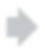

Thoracic diseases are very serious health problems that plague a large number of people. Chest X-ray is currently one of the most popular methods to diagnose thoracic diseases, playing an important role in the healthcare workflow. However, reading the chest X-ray images and giving an accurate diagnosis remain challenging tasks for expert radiologists. With the success of deep learning in computer vision, a growing number of deep neural network architectures were applied to chest X-ray image classification. However, most of the previous deep neural network classifiers were based on deterministic architectures which are usually very noise-sensitive and are likely to aggravate the overfitting issue. In this paper, to make a deep architecture more robust to noise and to reduce overfitting, we propose using deep generative classifiers to automatically diagnose thorax diseases from the chest X-ray images. Unlike the traditional deterministic classifier, a deep generative classifier has a distribution middle layer in the deep neural network. A sampling layer then draws a random sample from the distribution layer and input it to the following layer for classification. The classifier is generative because the class label is generated from samples of a related distribution. Through training the model with a certain amount of randomness, the deep generative classifiers are expected to be robust to noise and can reduce overfitting and then achieve good performances. We implemented our deep generative classifiers based on a number of well-known deterministic neural network architectures, and tested our models on the chest X-ray14 dataset. The results demonstrated the superiority of deep generative classifiers compared with the corresponding deep deterministic classifiers.